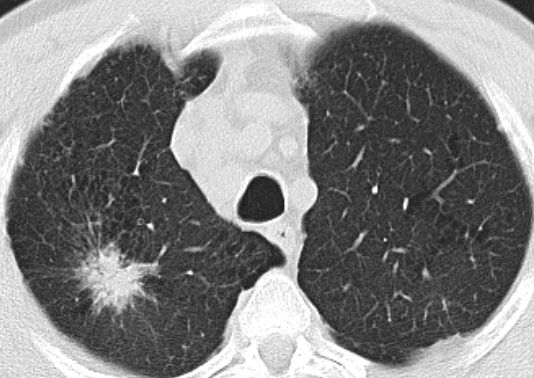

50-jähriger Mann mit einem Adenokarzinom im rechten Oberlappen![]() |